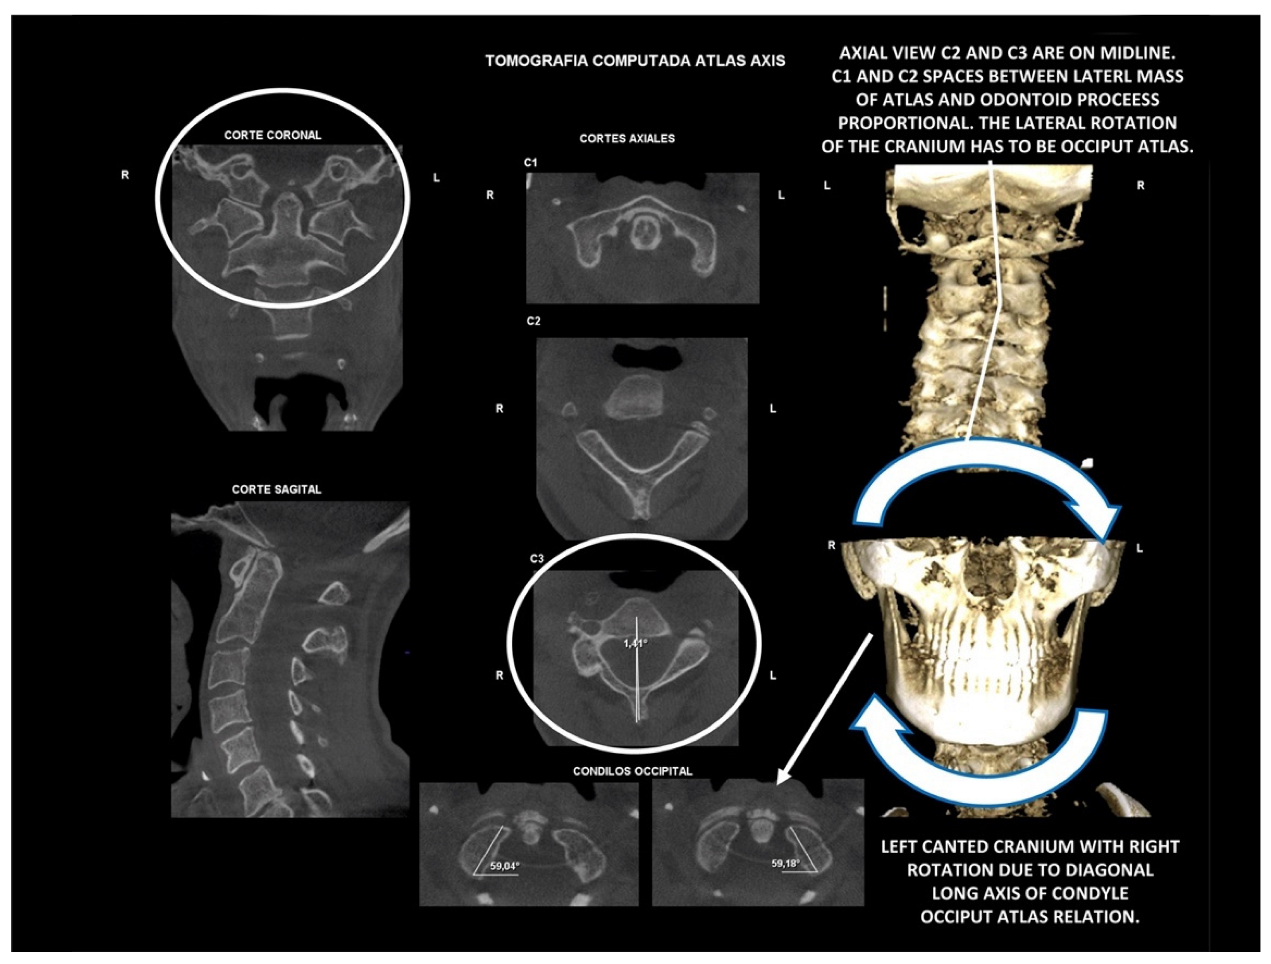

10.2. Computed Tomography of Cervical Spine

11.5. Axis and Atlas Derotation